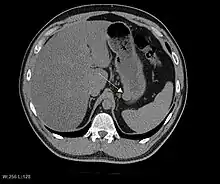

CT scanning is often undertaken (see the radiology section).

The purpose of radiologic imaging is to locate the lesion, evaluate for signs of invasion and detect metastasis. Features of GIST vary depending on tumor size and organ of origin. The diameter can range from a few millimeters to more than 30 cm. Larger tumors usually cause symptoms in contrast to those found incidentally which tend to be smaller and have better prognosis.[5][14] Large tumors tend to exhibit malignant behavior but small GISTs may also demonstrate clinically aggressive behavior.[15]

Barium fluoroscopic examinations and CT are commonly used to evaluate the patient with abdominal complaints. Barium swallow images show abnormalities in 80% of GIST cases.[15] However, some GISTs may be located entirely outside the lumen of the bowel and will not be appreciated with a barium swallow. Even in cases when the barium swallow is abnormal, an MRI or CT scan must follow since it is impossible to evaluate abdominal cavities and other abdominal organs with a barium swallow alone. In a CT scan, abnormalities may be seen in 87% of patients and it should be made with both oral and intravenous contrast.[15] Among imaging studies, MRI has the best tissue contrast, which aids in the identification of masses within the GI tract (intramural masses). Intravenous contrast material is needed to evaluate lesion vascularity.

Preferred imaging modalities in the evaluation of GISTs are CT and MRI,[17]: 20–21 and, in selected situations, endoscopic ultrasound. CT advantages include its ability to demonstrate evidence of nearby organ invasion, ascites, and metastases. The ability of an MRI to produce images in multiple planes is helpful in determining the bowel as the organ of origin (which is difficult when the tumor is very large), facilitating diagnosis.

As the tumor grows it may project outside the bowel (exophytic growth) and/or inside the bowel (intraluminal growth), but they most commonly grow exophytically such that the bulk of the tumor projects into the abdominal cavity. If the tumor outstrips its blood supply, it can necrose internally, creating a central fluid-filled cavity with bleeding and cavitations that can eventually ulcerate and communicate into the lumen of the bowel. In that case, barium swallow may show an air, air-fluid levels or oral contrast media accumulation within these areas.[15][18] Mucosal ulcerations may also be present. In contrast-enhanced CT images, large GISTs appear as heterogeneous masses due to areas of living tumor cells surrounding bleeding, necrosis or cysts, which is radiographically seen as a peripheral enhancement pattern with a low attenuation center.[14] In MRI studies, the degree of necrosis and bleeding affects the signal intensity pattern. Areas of bleeding within the tumor will vary its signal intensity depending on how long ago the bleeding occurred. The solid portions of the tumor are typically low signal intensity on T1-weighted images, are high signal intensity on T2-weighted images and enhanced after administration of gadolinium. Signal-intensity voids are present if there is gas within areas of necrotic tumor.[16][19][20]